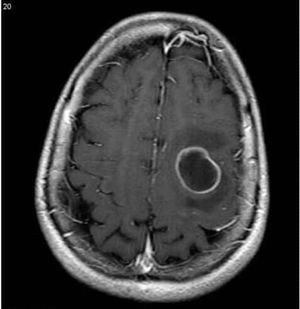

Diagnosis

What is this??